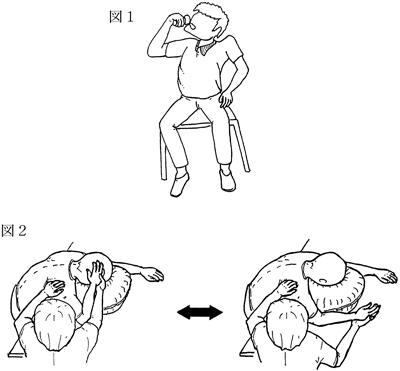

53歳の男性。脳出血による右片麻痺。ブルンストローム法ステージは上肢IV・手指IIIでやや痙縮が強い。麻痺側でコップの水を飲んでもらったところ図1のような反応がみられた。このような反応を軽減するための訓練として図2のような動作を行う際に注意すべき点で適切でないのはどれか。

1

麻痺側上肢の運動に抵抗をかける。

2

麻痺側肩関節は外旋位に保持する。

3

非麻痺側上肢をリラックスさせる。

4

麻痺側肩甲帯の前方突出を保持する。

5

頸部と体幹は軽度屈曲を保持する。